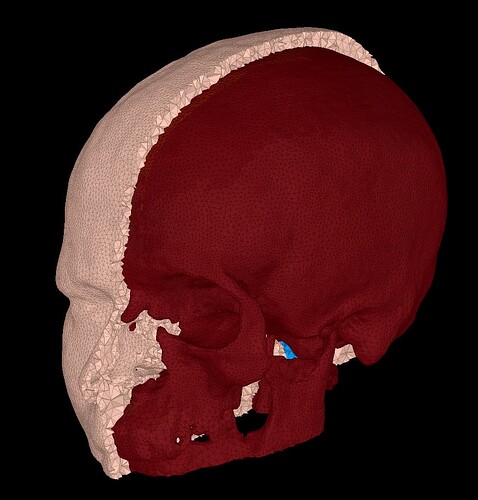

As a matter of fact, while the FEM model seems to do a good tissue characterisation, all the surfaces I have extracted within Brainstorm are wrong. For example, the scalp seems to have some skull embedded within

or, for example, the skull seems the CSF(?)